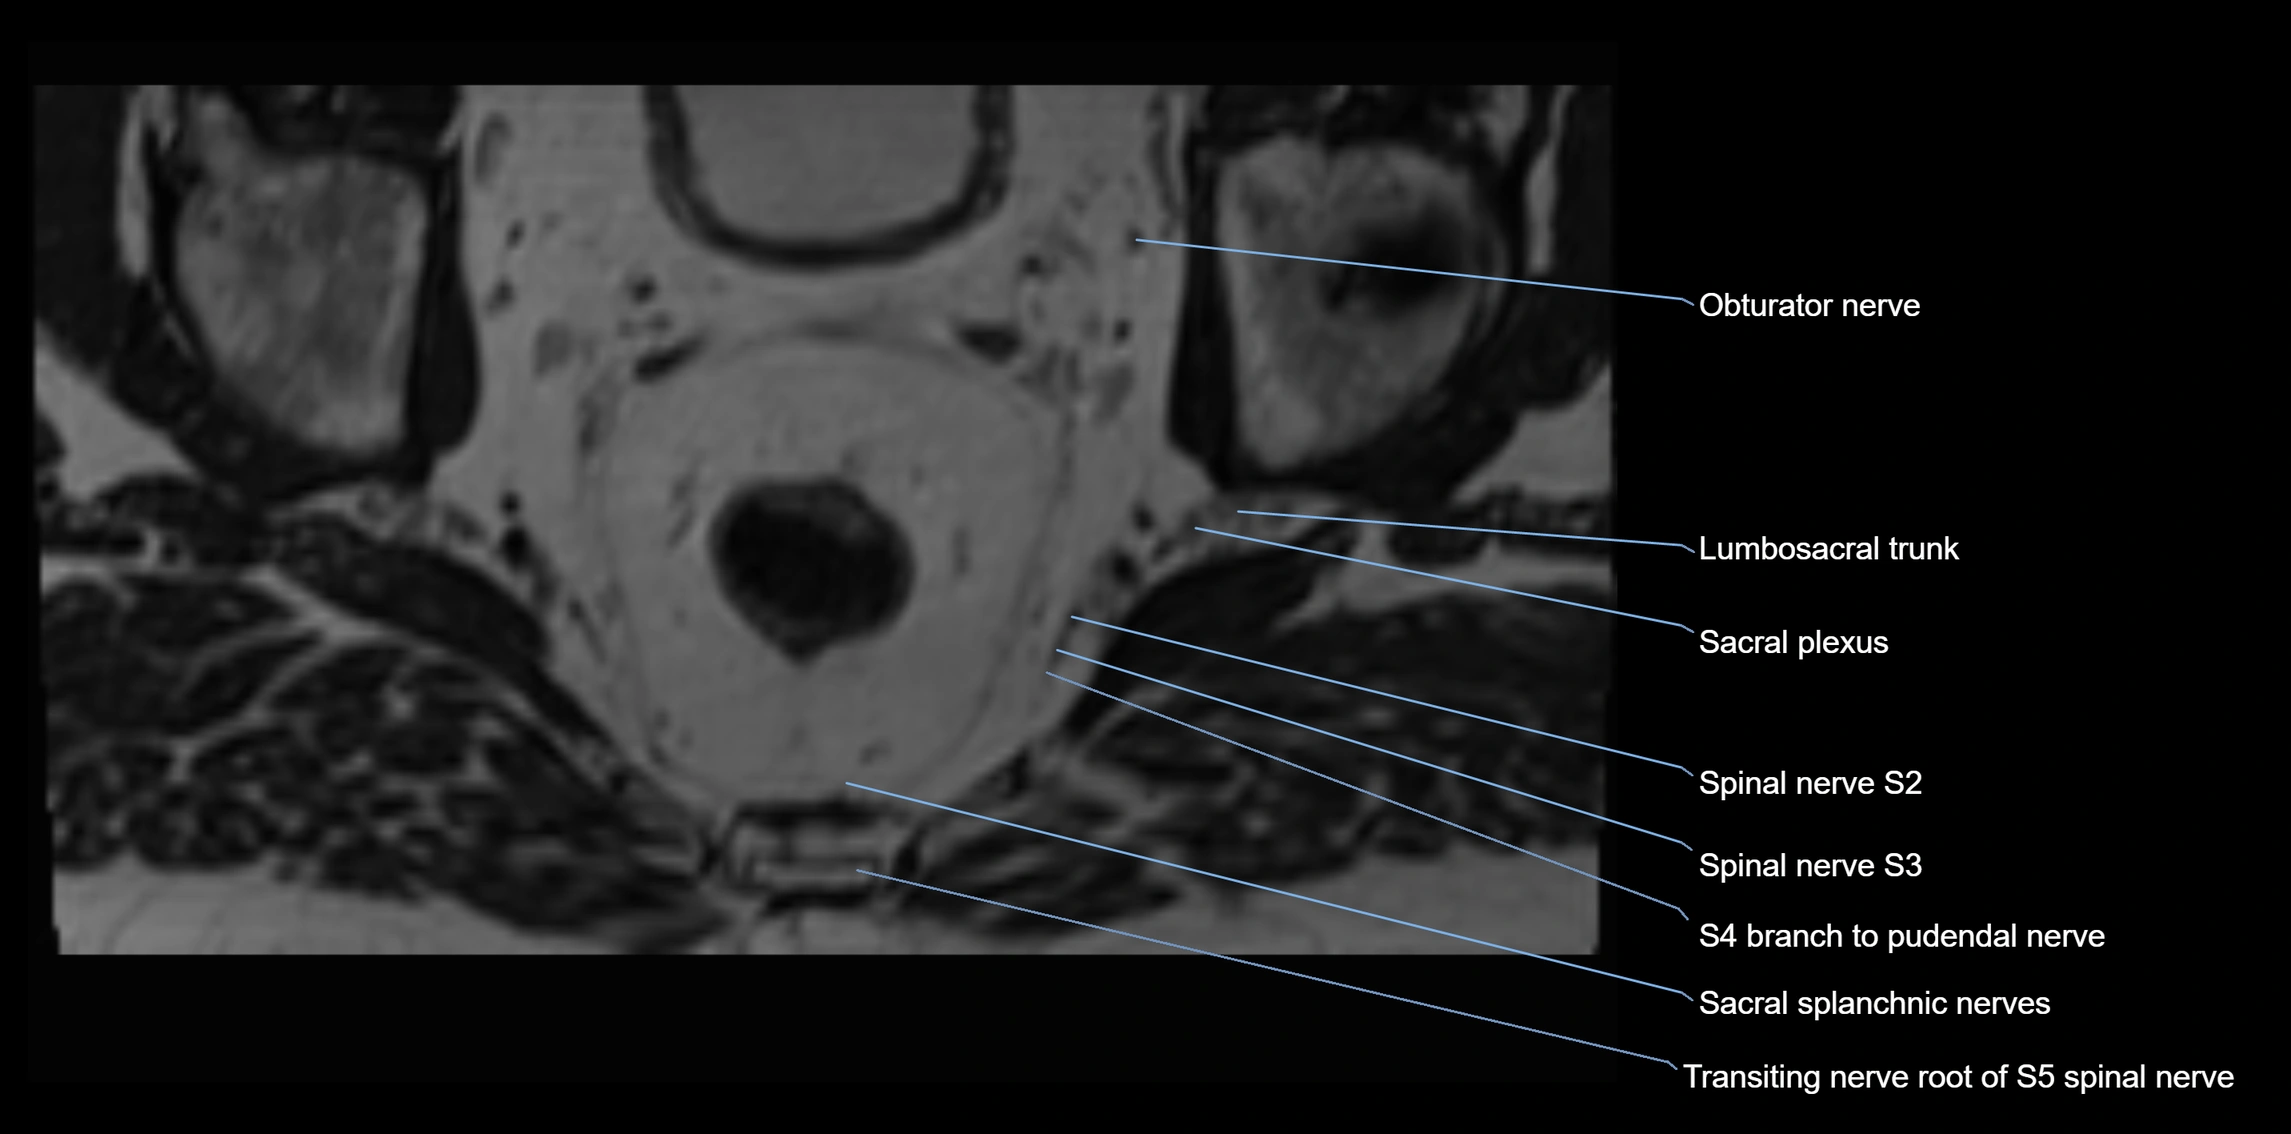

MRI image

image